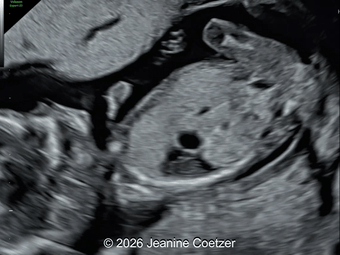

A 30-year-old G2P1, with an unremarkable history, presented to our office in the 21st week of her pregnancy for a routine second-trimester screening. Our examination revealed the following findings: